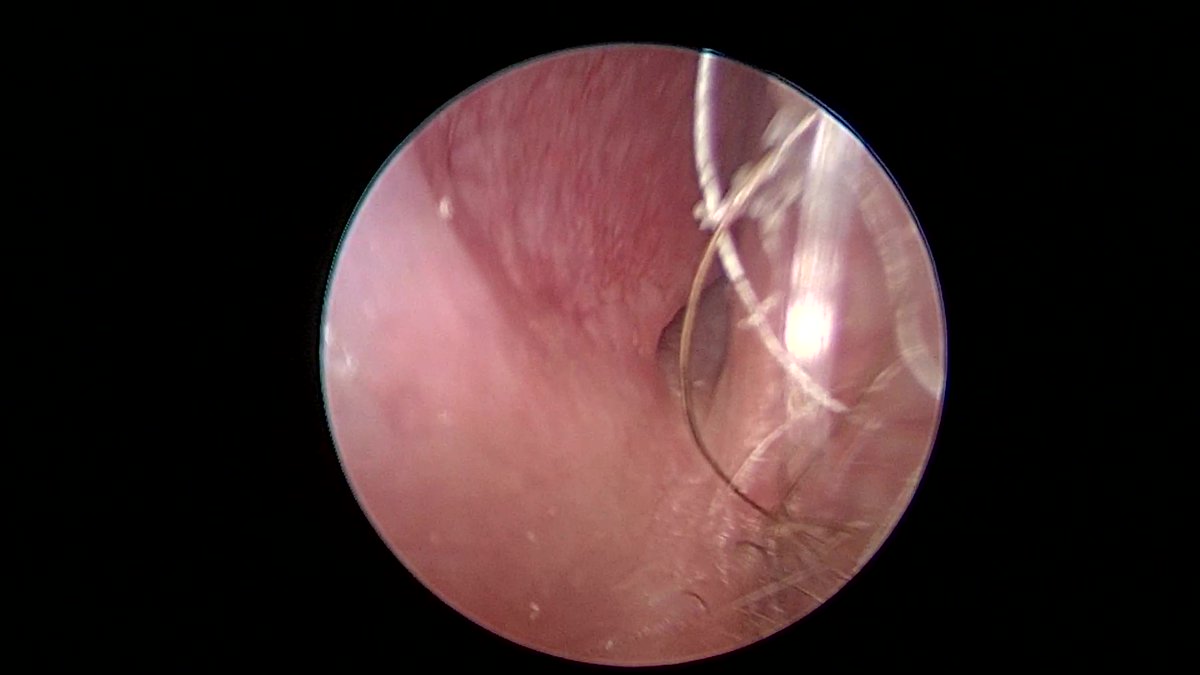

@ent_ams @JohnCraigNose @henryfordent What's under the microscope?

@JohnCraigNose @TroyWoodardMD @henryford Great case! A few questions from a trainee: When do you place packing (higher flow leak? Larger defect? )Can you link to the adhesive used? What kind of eye effects do you see (or not) with taking the vidian?